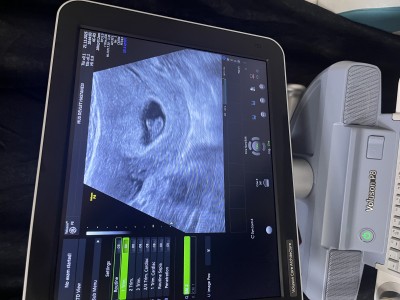

Gebelik haftası 7+1

Bazen kese göre değişiyor canım yuvarlak olursa  kız derler erkek olanda var şekilli olursa erkek olurdiyorlar  bende şekilli  bebeğim erkek 7 haftalık fotoğrafı vardı

Yani benim kesem şekilli mi

Şekilli gibi ama işte belli olmuyor canım dediğim gibi şekilli olup kız olanida var yuvarlak olup erkek olanıda en iyisi beklemek

Keseye göre erkek 😊